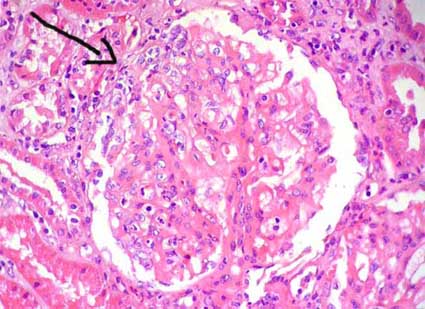

AJKD Atlas Of Renal Pathology: Diabetic Nephropathy

Diabetic nephropathy with tubular basement mem-brane thickening in nonatrophic tubules (electron microscopy).-Atlas of Renal Pathology II e38 Am J Kidney Dis. 2015;66(5):e37-e38. Title: AJKD Atlas of Renal Pathology: Diabetic Nephropathy Author: ... Read Content

Renal Morphologic Lesions Reminiscent Of Diabetic Nephropathy

Renal Morphologic Lesions Reminiscent of Diabetic Nephropathy Kirtee Raparia, MD; Irtaza Usman, MS; Yashpal S. Kanwar, MD, PhD tubular ECMs is associated with systemic disorders, such as myeloma. This process is characterized by the deposition of ... Read More